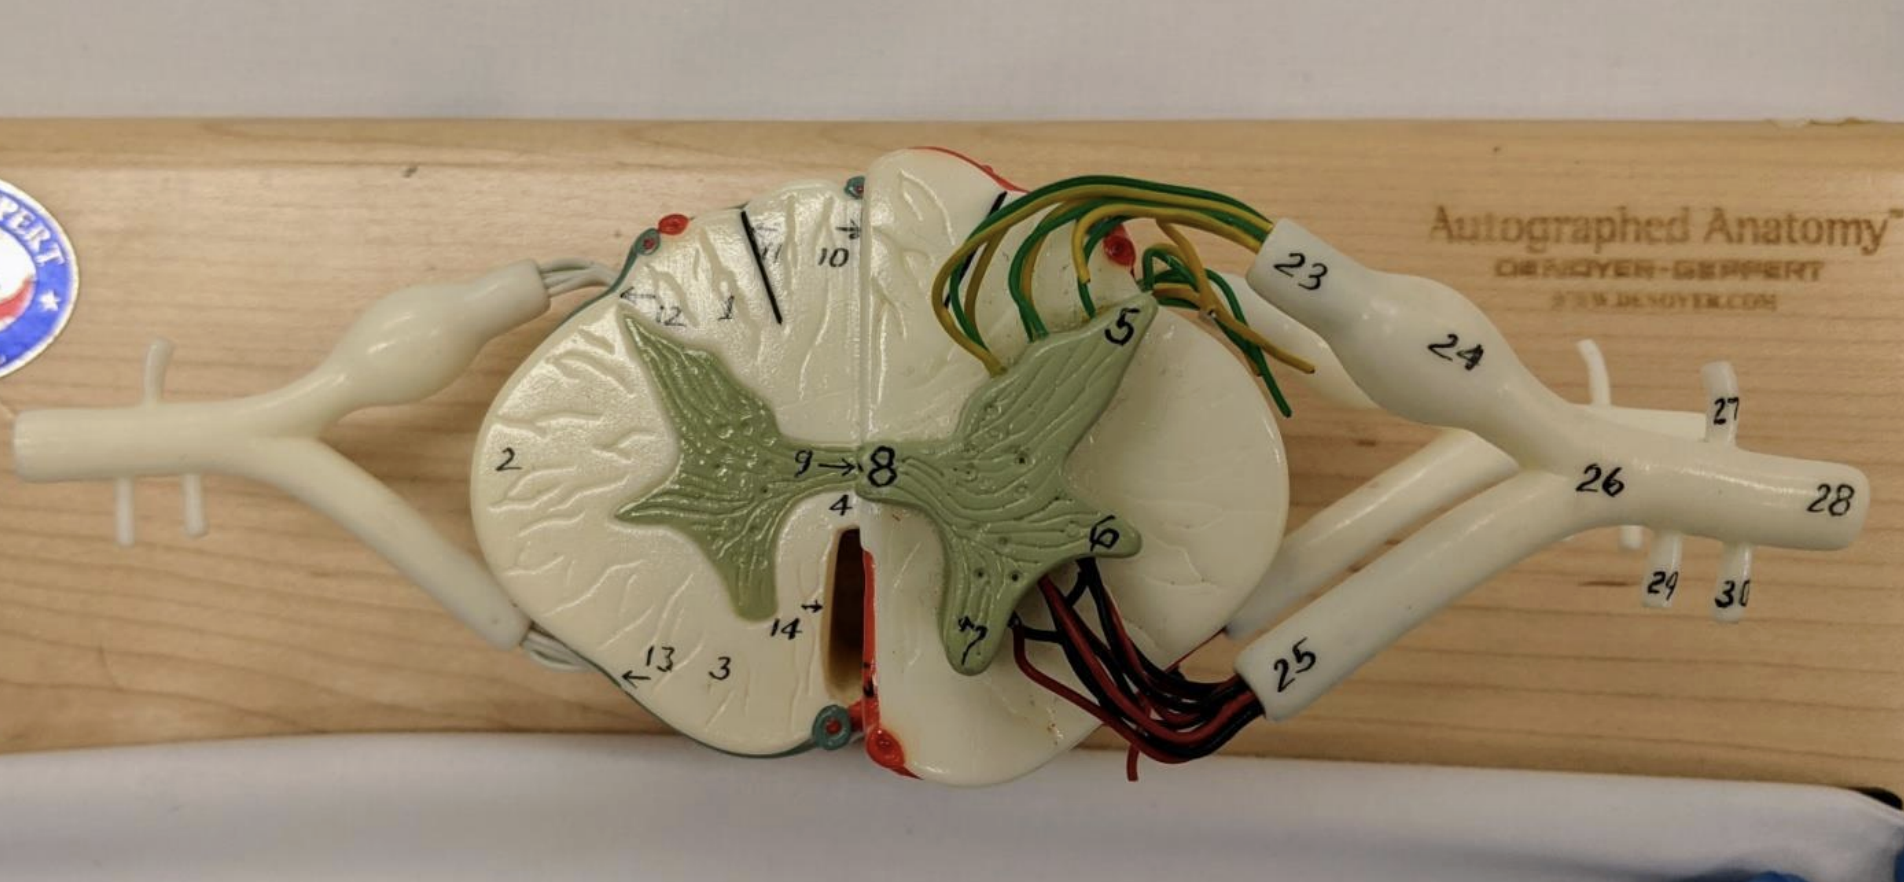

Anterior median fissure

Posterior median sulcus

Posterolateral

Anterolateral sulci

Ventral and dorsal rami

Rami communicantes

Anterior and posterior spinal arteries

The arterial supply of the spinal cord + origins

Anterior spinal artery that originates inside the cranium from branches off the vertebral arteries.

Two posterior spinal arteries that originate in the cranium as branches off the vertebral arteries or the posterior inferior cerebellar arteries, and descend along the posterolateral sulci